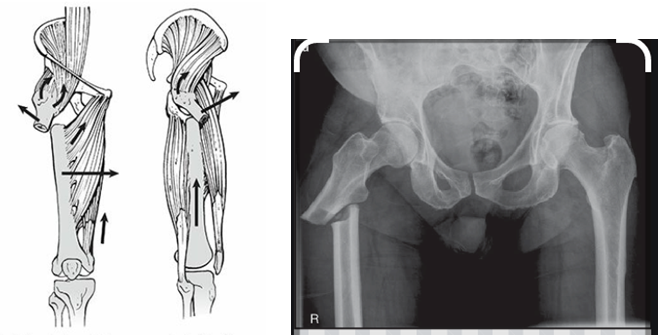

Gãy dưới mấu chuyển thường ổ gãy bị lệch nhiều do các cơ vùng đùi, háng rất lớn và co kéo các phần xương gãy

CHỤP XQUANG

Sau khi khám và đánh giá sơ bộ, bác sĩ sẽ cho chụp X quang vùng đùi, kể cả đầu gối

Tùy hình ảnh gãy trên Xquang mà bác sĩ sẽ phân loại kiểu gãy ở mức độ nào theo phân loại Russel Taylor. Việc phân loại này sẽ giúp bác sĩ lựa chọn dụng cụ kết hợp xương thích ứng với từng kiểu gãy cụ thể mà bệnh nhân đang có.